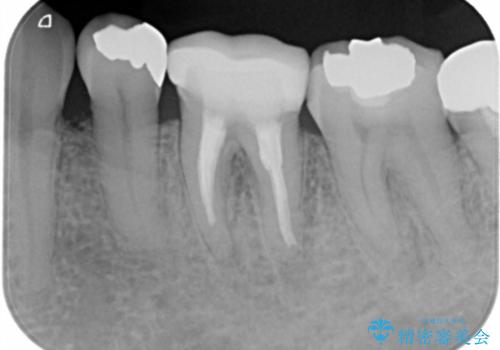

- 左下5番の銀歯をセラミックにやり変え希望の患者様です。

切削量を考慮し、セラミックインレーでの治療を選択しました。

銀歯直下のう蝕を除去しCRで裏層を行った上で、形成・印象を行っています。